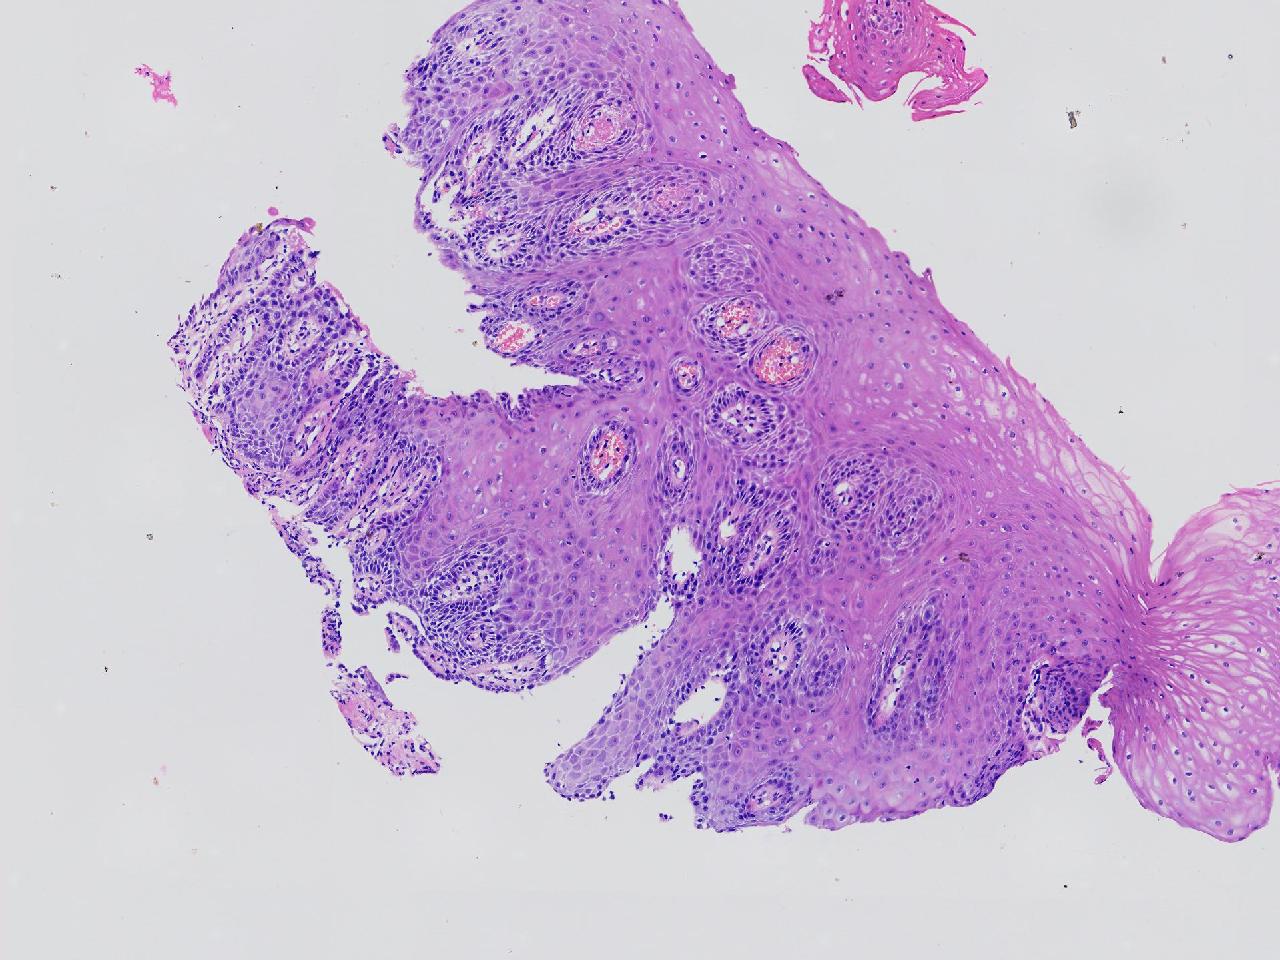

男,62岁,贲门口齿状线上见条状糜烂,活检1块,质软。

贲门口活检

灰白色不整形软组织1块,直径0.2厘米。

鳞皮乳头状增生伴慢性炎。